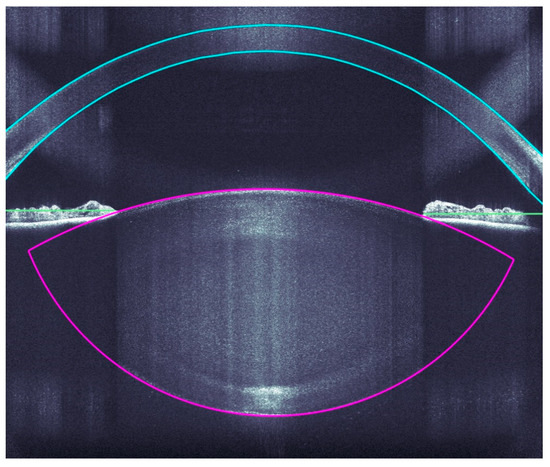

A very accurate OCT detection of the ocular structures allows a very precise incision of the clear corneal accesses, arcuate incisions, capsulotomies, and lens fragmentations by the Femtosecoond laser. The OCT imaging covers the corneal surfaces (anterior and posterior), iris, pupil, and anterior and posterior lens capsule (Figure 2).

Figure 2.

Intraoperative analyses of all ocular structure.

The decisive factor in OCT is the three-dimensional analysis, which fully identifies the anatomical structures and automatically suggests the cutting positions with the inclusion of an additional safety distance (Figure 3).

Figure 3.

The planned cutting lines and areas are marked grey, the red bars are the calculated safety distances.